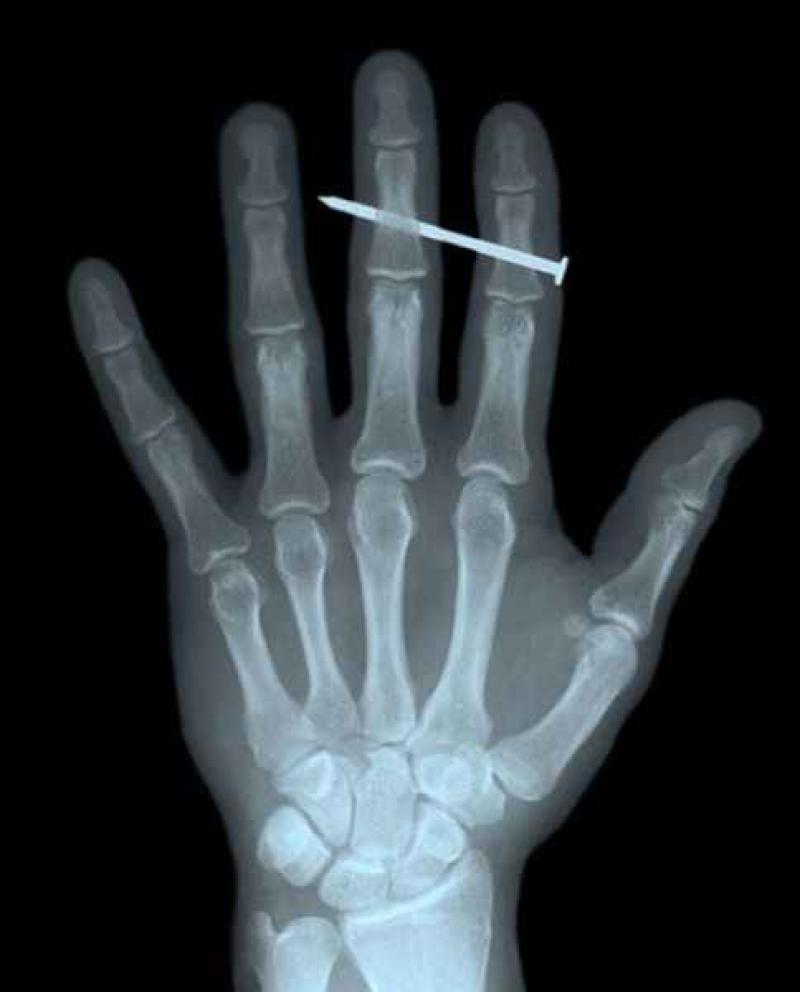

Röntgenfoto's zijn een medische uitvinding die ons al decennia lang helpt. Ze geven een nieuw gezichtspunt als het gaat om het vinden en behandelen van inwendige verwondingen. De machines kunnen opmerkelijke beelden vastleggen van het menselijk lichaam en ze documenteren vaak gruwelijke verwondingen. Een wonde van iemand zien, is al erg, maar als je ook kan zien wat de schade in het lichaam is, dat is nog veel erger. We hebben 12 tegelijk fascinerende, gruwelijke en hilarische röntgenfoto's op een rijtje gezet. Stel jezelf maar eens de vraag hoe iemand ooit aan die verwondingen is gekomen. We beginnen nog rustig.